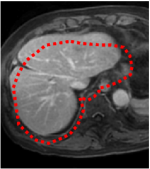

An example of CT/CBCT and MR/CBCT registration results are shown in figures 3 and 4, respectively. For both cases, the CBCT image (first column) was acquired intra-operatively after needle insertions and was employed as a reference for image registration. The pre-operative image is displayed before registration (second column), after PM-EA (third column) and after PM-EA+Evo (fourth column). The occurrence of patch shifts is reported for each spatial direction in panels (m–o): for each histogram, the shift with maximal occurrence is shown by the red dashed line. For panels (a–l), a ROI — manually defined on the CBCT image/encompassing the liver — is shown using red dash lines. Our visualization shows an improved correspondence of the contour of the liver with the manually defined liver boundary when the PM-EA solution is employed (see 3(c,g,k) and 4(c,g,k)). Moreover, an even better correspondence of the contour is observable using the PM-EA+Evo solution (see 3(d,h,l) and 4(d,h,l)).

Trans.

[X-Y]

CBCT

(a)

CT / No registration

(b)

CT / PM-EA

(c)

CT / PM-EA+Evo

(d)

Sag.

[X-Z]

(e)

(f)

(g)

(h)

Cor.

[Y-Z]

(i)

(j)

(k)

(l)

(m)

(n)

(o)